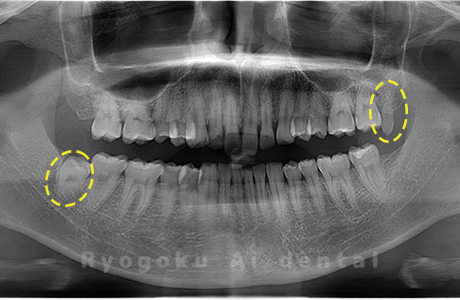

Case02

- 原因

- 下顎の水平埋伏智歯

- 治療内容

- 下顎の水平埋伏智歯を抜歯

<リスク・副作用>

手術後は痛み、腫れ、痺れなどの副作用が生じる場合があります。